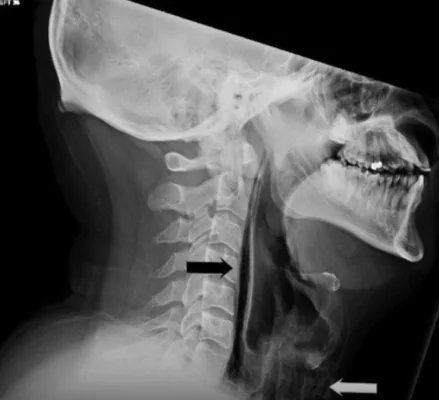

Рентген показал серьёзные повреждения — разрыв глотки, а в области шеи скопился воздух перед трахеей. Врачи предупредили, что помимо травм глотки, возможен разрыв барабанной перепонки или даже аневризмы головного мозга.